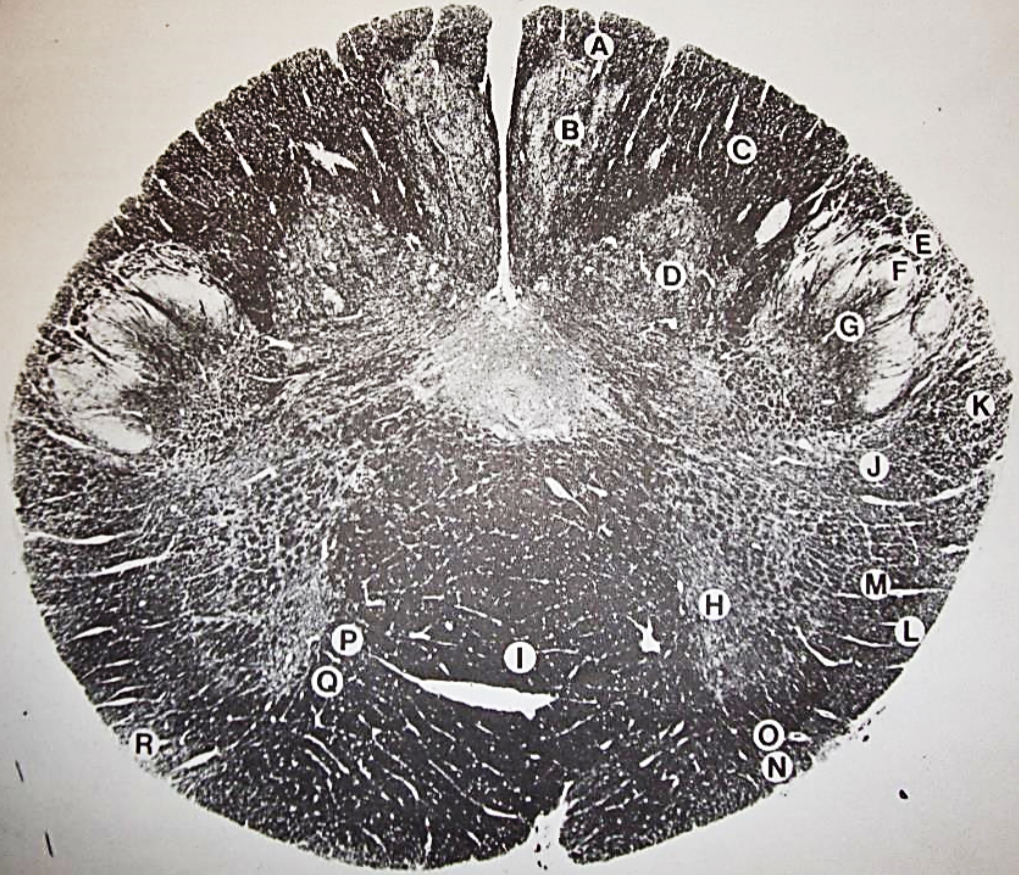

A

Lateral Cuneate nucleus

B

dorsal external arcuate fibers

C + D collectively

vestibular nuclei

C + D collectively

vestibular nuclei

E

dorsal motor nucleus of vagus nerve

F

solitary fasciculus

G

solitary nucleus

H

nucleus ambiguous

I

fascicles of glossopharyngeal nerve

J

hypoglossal nucleus

K

fascicles of hypoglossal nerve

L

dorsal longitudinal fasciculus

M

central tegmental tract

N

inferior olivary nucleus

R

inferior cerebellar peduncle

S

spinal trigeminal tract

T

spinal trigeminal nucleus

U

ventral trigeminothalamic tract

V

pyramidal (corticospinal) tract

W

rubrospinal tract

X

anterior spinocerebellar tract

Y

spinal lemniscus

Z

medial longitudinal fasciculus

a

tectospinal tract

b

medial lemniscus

c

vagus nerve

d

inferior salivatory nucleus